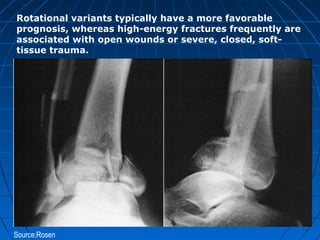

Rotational variants typically have a more favorable

prognosis, whereas high-energy fractures frequently are

associated with open wounds or severe, closed, soft-

tissue trauma.